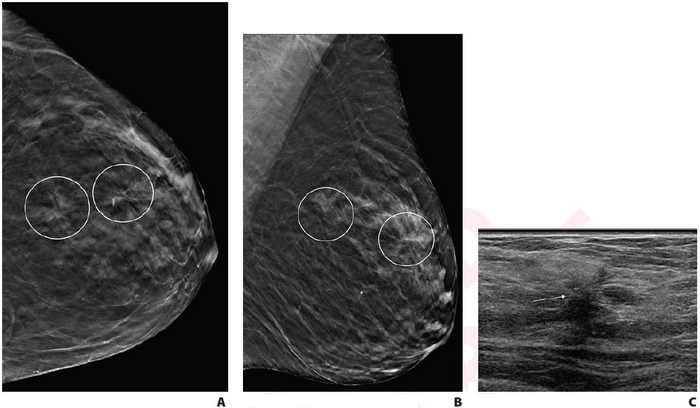

Single vs. multiple architectural distortion on digital breast tomosynthesis

Leesburg, VA, July 27, 2022 According to ARRS’ American Journal of Roentgenology ( AJR ) , for patients with multiple architectural distortion (AD) identified on digital breast tomosynthesis (DBT), biopsy of all areas may be warranted, given the variation of pathologic diagnoses across AD in individual patients.

“Multiple AD, compared with single AD, was significantly more likely to yield high-risk pathology, but there was no significant difference in yield of malignancy,” wrote corresponding author Lilian C. Wang , MD, of Northwestern Medicine. “In patients with multiple AD, multiple ipsilateral or contralateral AD commonly varied in pathologic classification: benign, high risk, or malignant.”

Wang and colleagues’ retrospective study included 402 patients (mean age, 56 years) who underwent image-guided core needle biopsy of AD visualized on DBT between April 7, 2017, and April 16, 2019. Patients were grouped in the single or multiple AD cohort based on the presence of distinct AD areas noted in the clinical report, while the pathologic diagnosis for each AD was based on the most aggressive pathology identified on either biopsy or surgical excision (if performed).

Ultimately, compared with single AD, multiple AD showed a higher frequency of high-risk pathology (53.0% vs. 32.5%, p=.002) but no significantly different frequency of malignancy on a per-lesion or per-patient basis (31.8% vs. 28.2%, p=.56). In 8/24 patients with ≥2 ipsilateral biopsied AD, the ipsilateral areas varied in terms of most aggressive pathology; in 5/10 patients with contralateral biopsied AD, the contralateral areas varied in most aggressive pathology.